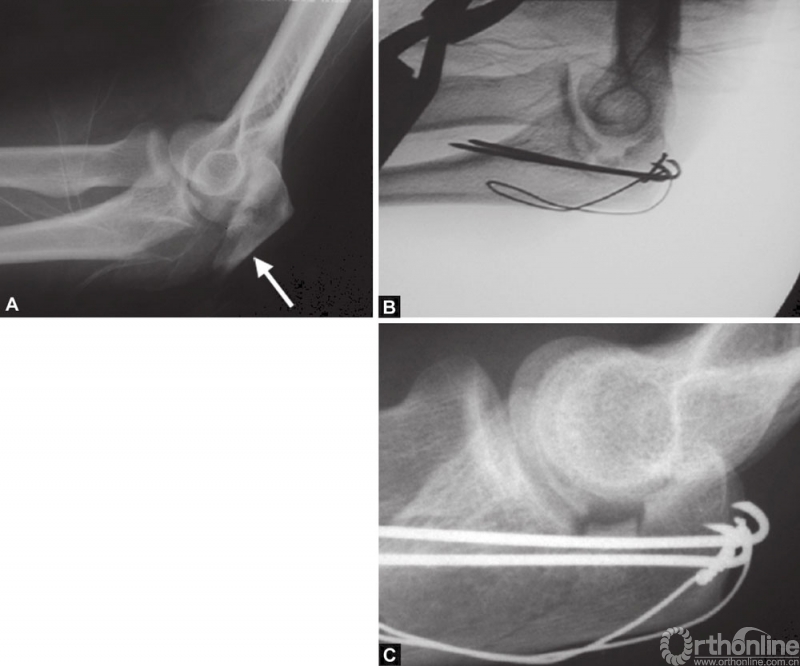

图3A~C关节压缩骨折在鹰嘴斜位片中完全隐匿。在箭头的部位变窄可能是一个提示。如果不知道这种可能性,医生就会忽略该手术X线片检查中明显的关节面压缩骨折。术后标准的侧位片良好地显示了关节面压缩骨折。该医生未能完成最初的手术目标